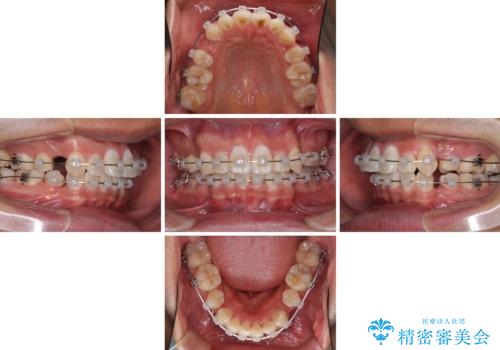

- クリアブラケット

- 3年3ヶ月

- 10-30回